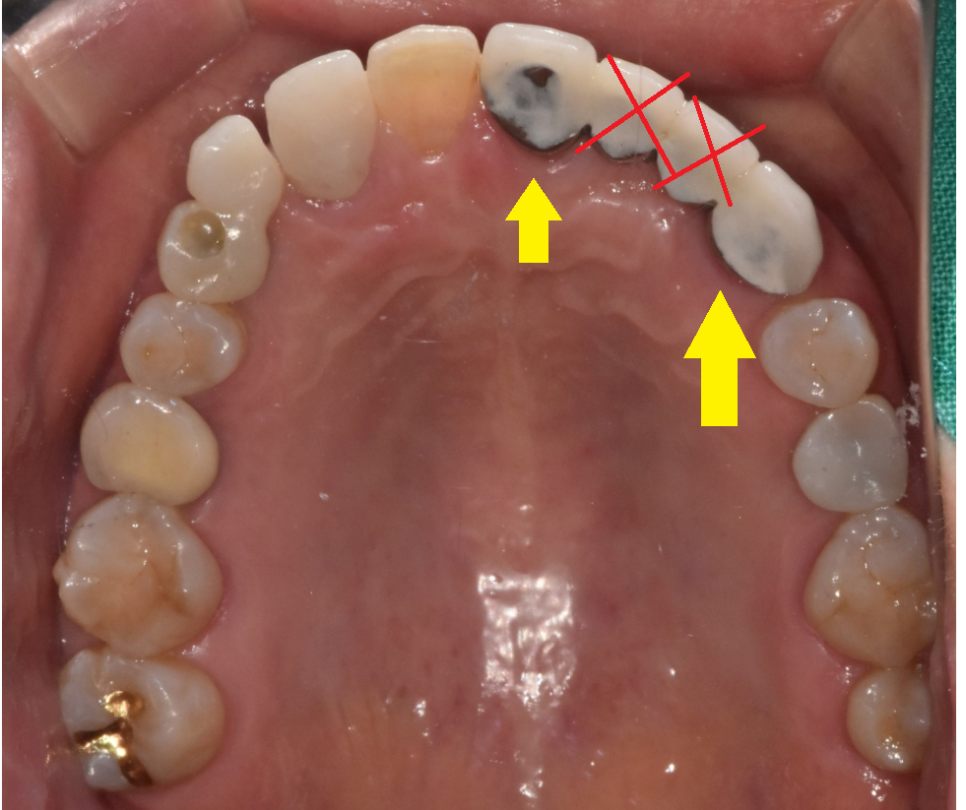

그리고 치아가 상실된지 오래되어

치아가 쓰러져 자리가 부족할 때

임플란트 수술 대안으로 브릿지를 합니다.

위에 환자분도 치아가 빠진지 워낙 오래되어

저 좁은 공간에 치아 3개가 들어가야했습니다.

240408

임플란트는 뼈에 심는건데

공간이 안나오면 브릿지로 대체하죠~